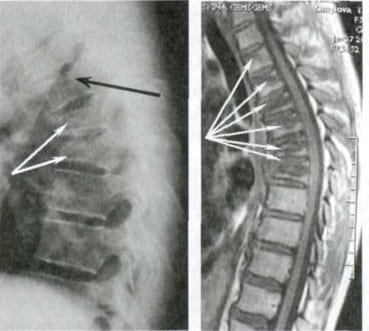

Veja esta radiografia. É a coluna vertebral de um homem de 44 anos, mas parece... a de um idoso. Antigamente, este tipo de lesão manifestava-se mais tarde, a partir dos 60 anos, mas hoje em dia é muito comum em pessoas com cerca de 40 anos. Estas alterações progridem com a idade e ignorá-las pode levar à perda total da mobilidade.

Coluna vertebral de um paciente de 44 anos: tudo começou com uma simples dor, mas numa semana surgiu uma hérnia e, em duas semanas, um deslocamento das vértebras, compressão do nervo e necessidade de cadeira de rodas.